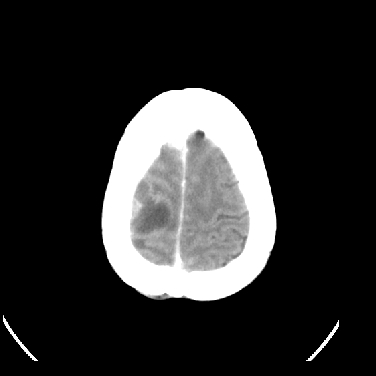

男,45岁,左侧肢体乏力1周。ex:胸片示:两肺团块状、斑片状密度增高影,其内可见小空洞。支纤镜、经皮肺穿示:干酪样物。

结合病史考虑结核性脑炎脑膜炎,伴脑脓肿形成

考虑右侧顶叶脑脓肿形成。

同意“考虑结核性脑炎脑膜炎,伴脑脓肿形成”的意见,不轻易怀疑肿瘤。

考虑结核性脑炎脑膜炎,伴脑脓肿形成。

考虑右侧顶叶脑脓肿(结核性?)。

结核性脑脓肿可能大

结合病史考虑结核性脑炎脑膜炎,伴脑脓肿形成,囊变转移瘤不除外